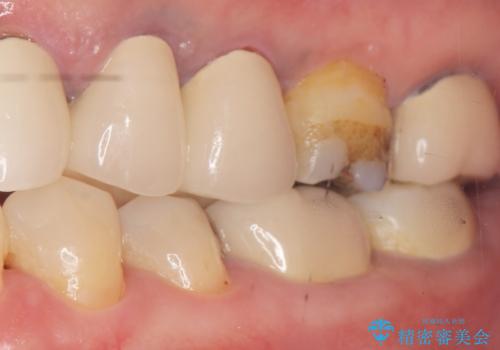

- 詰め物の境目が黒いことを気にされ、来院された患者様です。

精査したところ、左下の奥歯(左下5)のプラスチックの詰め物と歯の境目が虫歯になり、黒くなっていました。